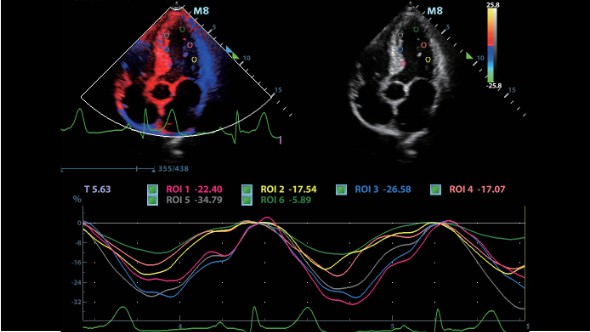

При работе со сложными и неотложными клиническими сценариями в повседневной практике растет потребность в высокопроизводительных переносных ультразвуковых диагностических системах в сфере общей визуализации, эхокардиографии

и в местах оказания медицинской помощи.

Клинические изображения